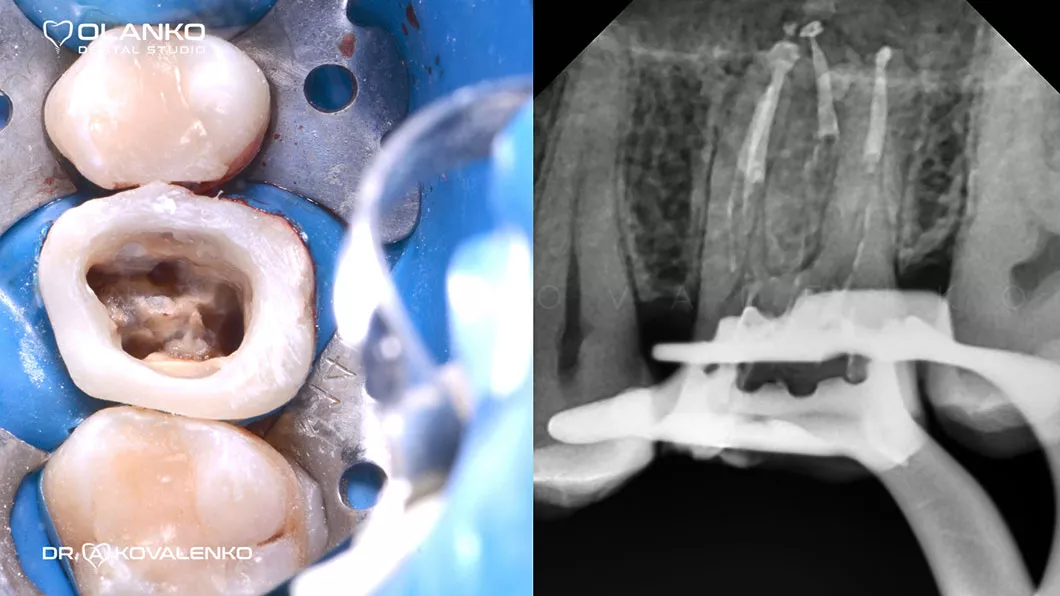

ВИДЕО ЛЕЧЕНИЯ КОРНЕВЫХ КАНАЛОВ ЗУБА ПОД МИКРОСКОПОМ С ПОСЛЕДУЮЩИМ ВОССТАНОВЛЕНИЕМ КЕРАМИЧЕСКОЙ КОРОНКОЙ

Лечение корневых каналов зуба с использованием микроскопа, на сегодняшний день, является золотым стандартом мировой стоматологической практики. Сложная система корневых каналов в зубе имеет очень малый диаметр и индивидуальную анатомию, поэтому врач, работающий без увеличения, не может качественно очистить и найти все корневые каналы на ощупь.

Важным преимуществом Olanko dental studio (Оланко) г. Бровары является то, что выполнение всех этапов лечения корневых каналов мы проводим только под контролем операционного дентального микроскопа!

На примере перелечивания корневых каналов верхнего жевательного зуба

Мы имеем огромный клинический опыт лечения зубов со сложной анатомией (искривлёнными, склерозированными каналами), а также повторного перелечивания каналов с кистами, гранулемами, сломанными инструментами, с последующими отличными результатами заживления очагов хронического воспаления.